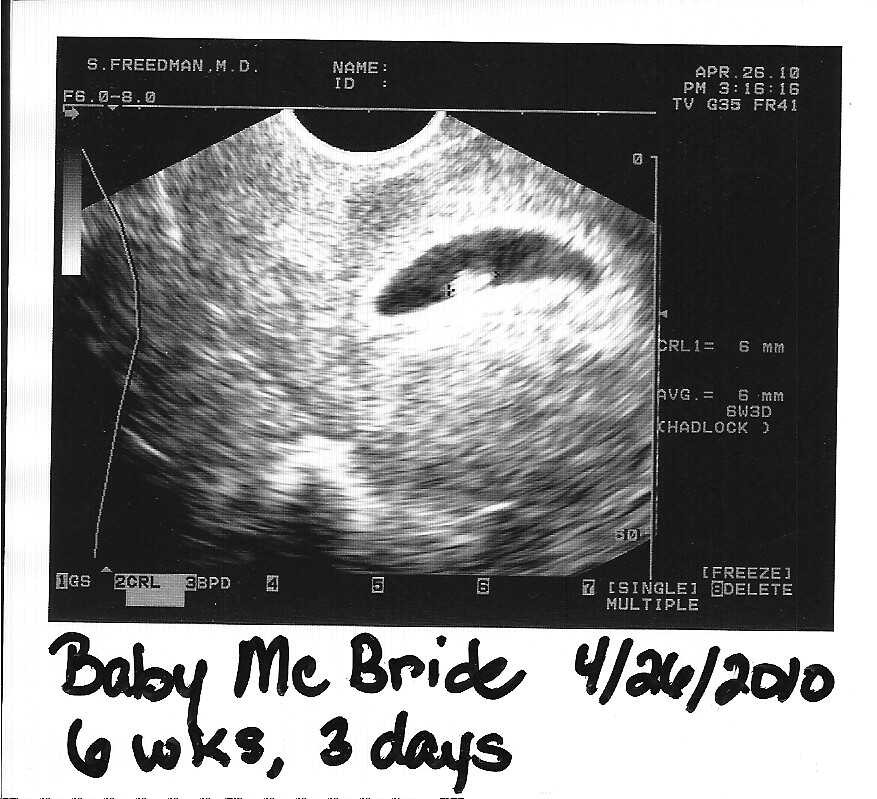

Can i get pregnant after my tubes are tied and burnt, ultrasound pics 6 …

50+ Great 6 Week Ultrasound – japan anime image

Normal first trimester 6 weeks ultrasound. – Ultrasoundfeminsider …